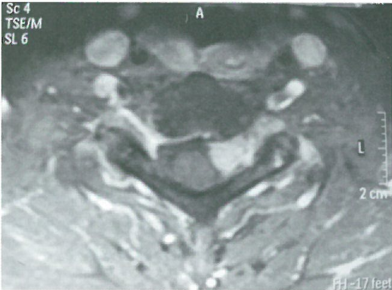

图1 肿瘤覆盖了颈长肌和横突孔。

在受累节段胸锁乳突肌内侧缘做纵行切口暴露椎体,在胸锁乳突肌和颈内静脉之间的间隙可以进行锐性分离,在暴露C4以上时注意保护副神经。将胸锁乳突肌拉向外侧,不需要游离大血管、气管和食管,将这些结构通过叶片拉钩拉向内侧。利用手指可触及椎体横突。它们被椎体前方肌肉覆盖(图)。于覆盖椎体前方肌肉的筋膜处沿交感神经链内侧纵行切开。